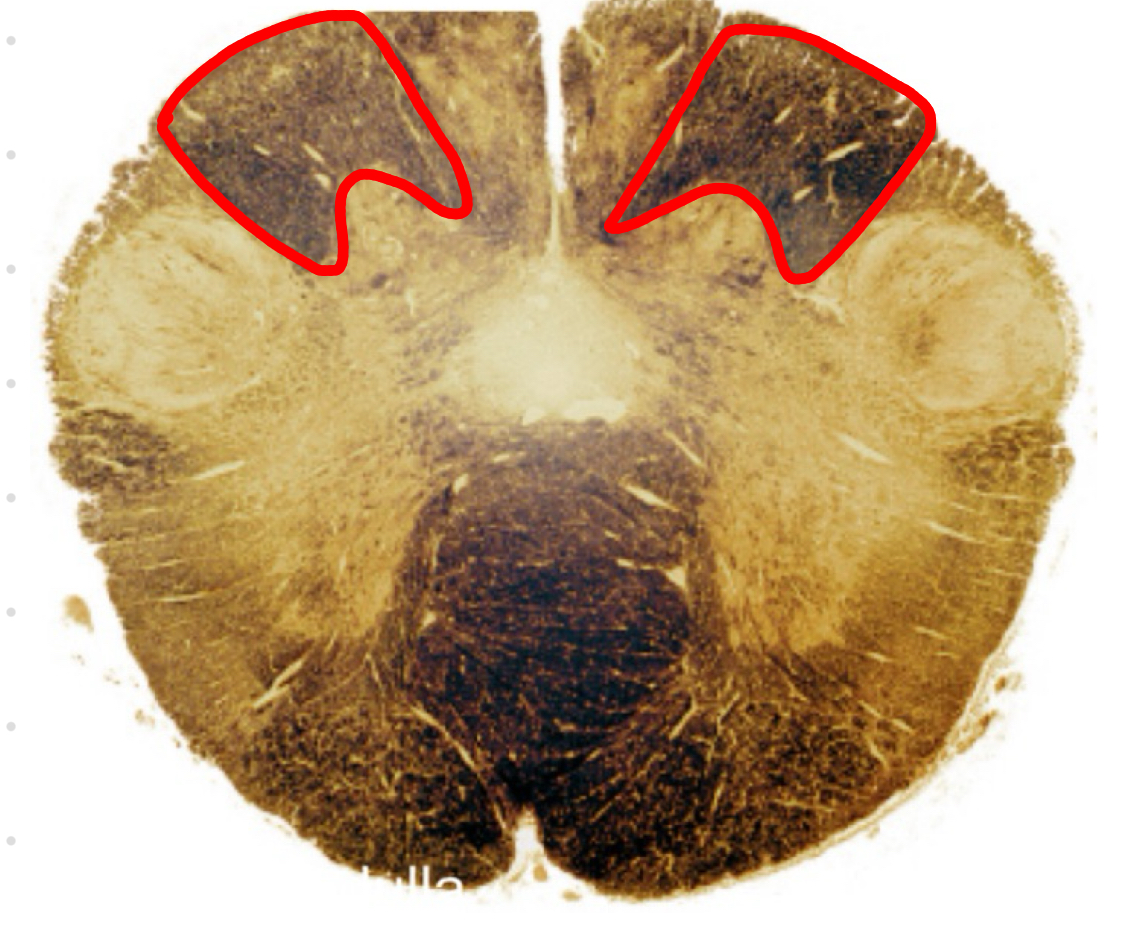

cuneate tract caudal medulla I

cuneate tract caudal medulla II